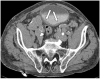

Amyloidosis comprises a rare spectrum of protein deposition diseases that diffusely or focally affect any organ. Amyloid's variable clinical presentation and nonspecific disease course often cause it to evade early diagnosis. This pictorial essay aims to familiarize radiologists with the pathophysiology of amyloidosis, to describe the basic classifications of amyloidosis, and to use multimodality imaging to illustrate its varied appearance throughout the body. This review highlights the diagnostic challenge of interpreting radiographic studies in patients with hematologic malignancies and concurrent amyloidosis. Radiologists should consider amyloid in chronically ill patients or patients with hematologic malignancies who have unusual/unexpected imaging findings.